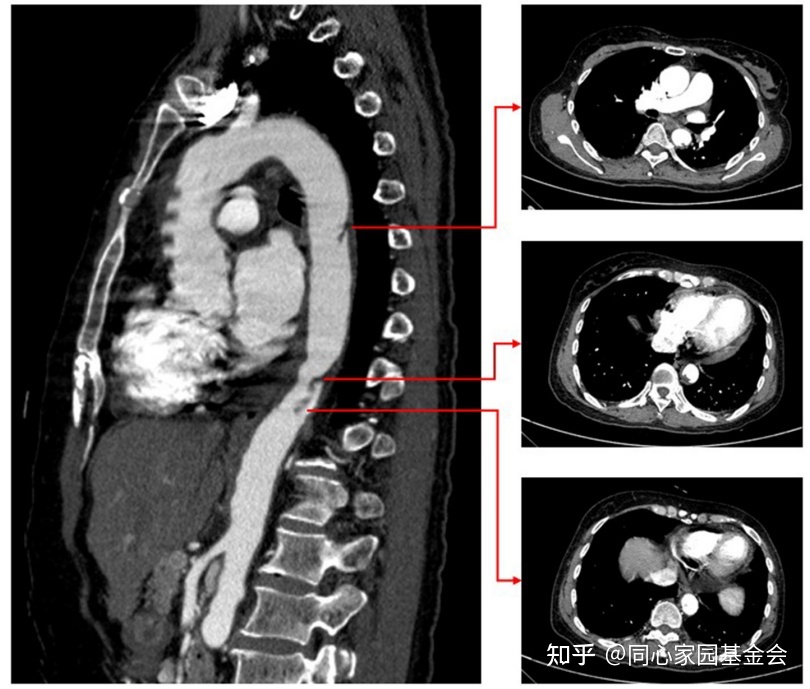

抗凝治疗10天后,CTA复查显示主动脉壁血栓明显变小(图4)。

图4:复查CTA 显示主动脉壁血栓显著变小。

原发性血小板增多症的药物治疗包括:抗凝治疗和用羟基脲进行细胞减灭治疗。另一方面,主动脉血栓的外科治疗与高死亡率和发生并发症的高风险相关,包括出血、脑和肠缺血以及急性肾衰竭。本病例的患者因原发性血小板增多症同时合并急性心肌梗死和主动脉血栓形成,由于患者左前降支此前置入了药物洗脱支架,因此需要进行双抗血小板治疗。如果选择急性手术治疗,出血的风险会非常高。因此,最终选择了药物治疗。幸运的是,经过阿司匹林,氯吡格雷,依诺肝素和羟基脲的治疗,患者的病情得以稳定,复查CTA 显示主动脉血栓显著变小。

原发性血小板增多症的主要治疗目标包括预防血栓复发。研究表明,口服抗凝剂联合细胞灭减疗法可能会降低原发性血小板增多症和静脉血栓栓塞症患者血栓复发的风险。然而,对于急性心肌梗死合并主动脉壁血栓形成患者的最佳抗栓策略和疗程尚不明确。基于本案病例经治疗主动脉血栓变小和D-二聚体水平降低,证明三联抗栓治疗是有效的。然而,长期的三联抗栓治疗可能会增加出血风险。因为原发性血小板增多症是一种血小板疾病,因此对于原发性血小板增多症伴有主动脉血栓形成患者,抗血小板治疗可能对于降低其血栓风险更为关键。本案患者出院时,其药物治疗包括:双重抗血小板治疗12个月(阿司匹林,氯吡格雷)和细胞灭减治疗。由于患者因经济原因拒绝再次进行CTA复查,我们要求患者提供血小板计数和D-二聚体水平随访数椐,以监测血栓风险。